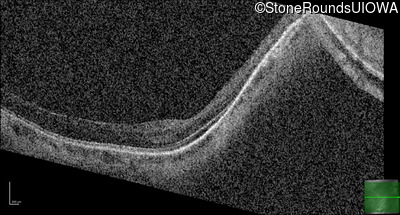

Age at visit: 41 years (Visit 2)

OD OS

This 41 year old woman was highly myopic as a child and experienced a rhegmatogenous retinal detachment OS at age 20.

Refraction OD:     -17.25 +1.00 x 93

Refraction OS:     -18.25 +3.50 x 56

The clinical features favoring the diagnosis of Sticker syndrome in this patient include extensive radial lattice degeneration, a personal and family history of rhegmatogenous retinal detachment, a history of cataract surgery before age 30 (and very high myopia before that), arthritis in her knees and hips and a slightly flattened mid-face.